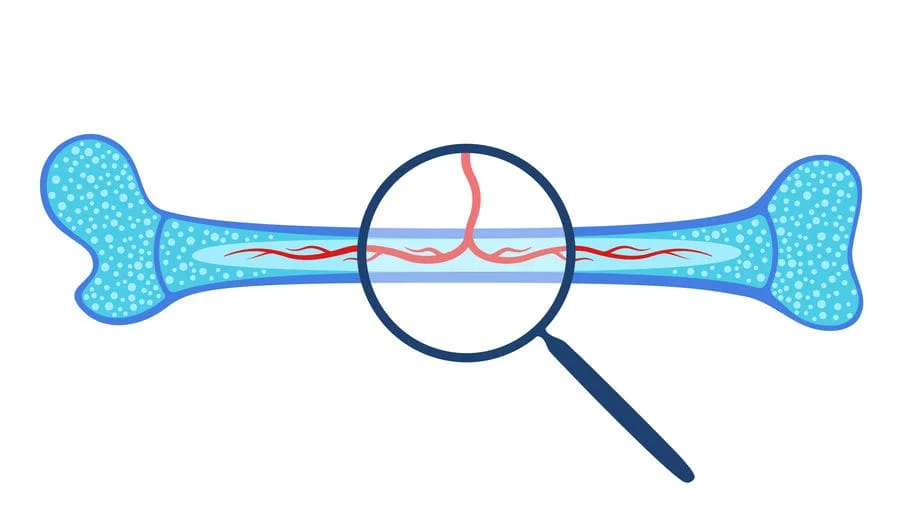

زرع نقي العظامإحدى العمليات التي يتم فيها استبدال نخاع العظام الغير صالح، ويحقن بدلًا منه خلايا جذعية، ونقي العظام أو بمصطلح آخر “نخاع العظام” عبارة عن نسيج صلب بعض الشيء يتواجد داخل العظام الطويلة.

وظيفة نقي العظام تتمثل في تكوين الدم لدى الكائنات الثديية والطيور، حيث ينتج ما يقارب نصف تريليون خلية دم بشكل يومي، ويشكل نقى العظام ما يقارب 4% من الوزن الكلي للجسم، وعملية زرع نقي العظام تُستخدم لمعالجة عديد من الأمراض الخطيرة التي سوف نتناول تفصيلًا في السطور القادمة.